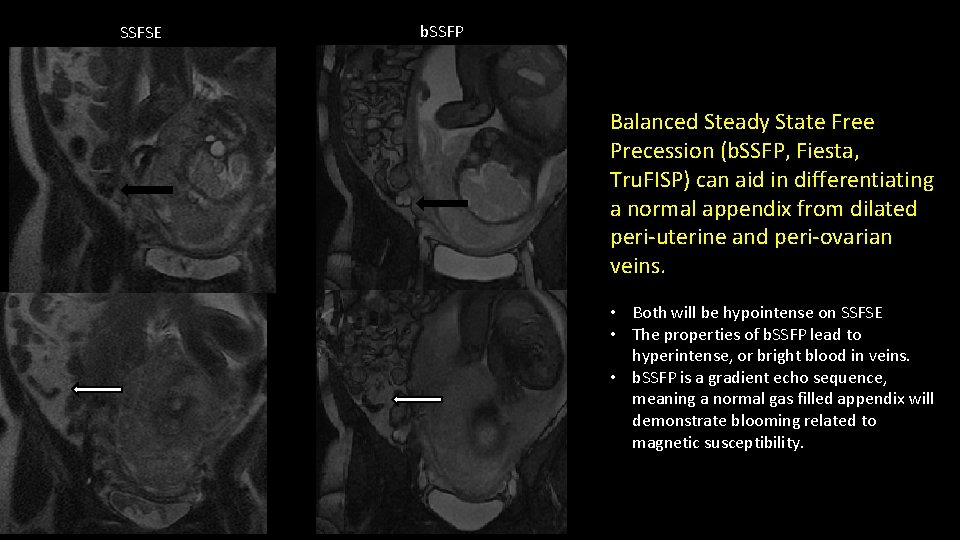

SSFSE b. SSFP Balanced Steady State Free Precession (b. SSFP, Fiesta, Tru. FISP) can aid in differentiating a normal appendix from dilated peri-uterine and peri-ovarian veins. • Both will be hypointense on SSFSE • The properties of b. SSFP lead to hyperintense, or bright blood in veins. • b. SSFP is a gradient echo sequence, meaning a normal gas filled appendix will demonstrate blooming related to magnetic susceptibility.